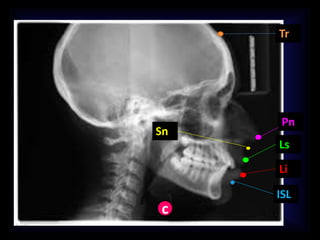

PUNTOS CEFALOMÉTRICOS EN

TEJIDOS SUAVES:

 Punto Cervical (C). Punto entre el área submental

y el cuello en el plano submental.

 Surco Labial Inferior (IIs). Punto encontrado en la

concavidad en el contorno del labio inferior entre

este último y el mentón.

 (Li) :Punto denotado entre el borde del bermellón

del labio inferior.

 (Ls) :Punto denotado entre el borde del bermellón

del labio superior.

 Pronasal (Pn) :Punto más prominente de la nariz

en el plano medio sagital.

c

ISL

Li

Ls

Pn

Sn

Tr

PUNTOS CEFALOMÉTRICOS EN TEJIDOSSUAVES:  Punto Cervical (C). Punto entre el área submental y el cuello en el plano submental.  Surco Labial Inferior (IIs). Punto encontrado en la concavidad en el contorno del labio inferior entre este último y el mentón.  (Li) :Punto denotado entre el borde del bermellón del labio inferior.  (Ls) :Punto denotado entre el borde del bermellón del labio superior.  Pronasal (Pn) :Punto más prominente de la nariz en el plano medio sagital.

PUNTOS CEFALOMÉTRICOS EN TEJIDOSSUAVES:  Stomion (St). Punto más anterior del contacto entre el labio superior y el labio inferior.  Stomion Inferior (Sti). Punto medio más alto del labio inferior.  Stomion Superior (Sts). Punto medio más inferior del labio superior.  Subnasal (Sn) Punto en el plano medio sagital donde la base de la nariz encuentra al labio superior.  Surco labial Superior (Sls). Punto que se encuentra en la concavidad en el contorno del labio superior entre subnasal y el labio superior.  Triquium (Tr). Punto de la línea del cabello en la frente. Si no hay cabello se calcula el lugar donde estuvo.